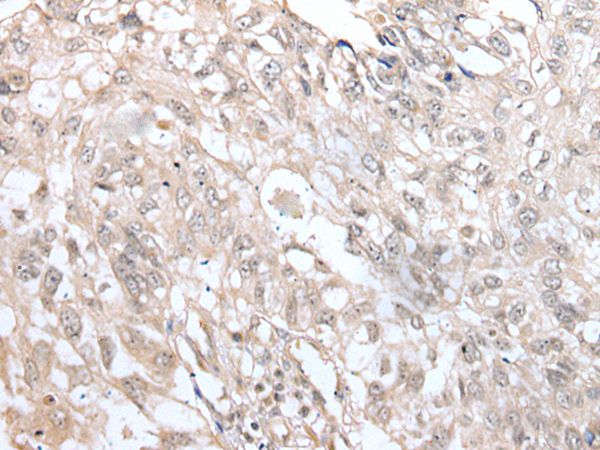

The image on the left is immunohistochemistry of paraffin-embedded Human lung cancer tissue using VRK3 Antibody at dilution 1/45, on the right is treated with fusion protein. (Original magnification: x200)

The image on the left is immunohistochemistry of paraffin-embedded Human esophagus cancer tissue using VRK3 Antibody at dilution 1/45, on the right is treated with fusion protein. (Original magnification: x200)